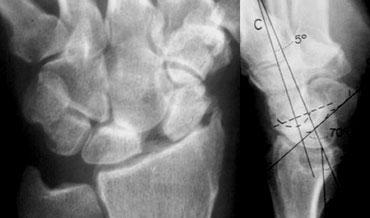

Vẽ các trục dọc của một số xương cổ tay trên phim chụp X-quang tư thế nghiêng và đo các góc giữa chúng là một phương pháp tốt để xác định mối quan hệ không gian giữa các xương cổ tay. Ba trục quan trọng nhất là các trục đi qua xương thuyền, xương nguyệt và xương đầu, được vẽ trên phim X-quang tư thế nghiêng.

Trục xương thuyền

Trục thực sự của xương thuyền là đường thẳng đi qua điểm giữa của cực gần và cực xa. Do điểm giữa của cực gần thường khó xác định, có thể sử dụng một đường gần song song được vẽ dọc theo các điểm mặt gan tay nhất của cực gần và cực xa của xương (hình minh họa).

TRÁI: Trục xương nguyệt được vẽ vuông góc với đường nối bờ gan tay xa và bờ mu tayPHẢI: Phim X-quang với trục xương nguyệt và xương thuyền được vẽ.

Trục xương nguyệt

Trục của xương nguyệt đi qua điểm giữa của diện khớp lồi ở phía gần và diện khớp lõm ở phía xa, và được xác định tốt nhất bằng cách tìm đường vuông góc với đường nối bờ gan tay xa và bờ mu tay của xương như minh họa ở hình bên trái.

Góc thuyền-nguyệt

Bình thường: 30 – 60°

Nghi ngờ bất thường: 60 – 80°

Bất thường: > 80° Điều này cho thấy mất vững cổ tay.

Trục xương đầu

Trục xương đầu nối điểm giữa của phần lồi gần của xương đốt bàn tay thứ ba với điểm giữa của mặt gần xương đầu.

Góc đầu-nguyệt

Bình thường: < 30°

Bất thường: > 30°. Điều này cho thấy mất vững cổ tay.

Trong hình bên trái, góc thuyền-nguyệt được đo là 105 độ. Như đã đề cập, góc này được coi là bất thường khi lớn hơn 80 độ.